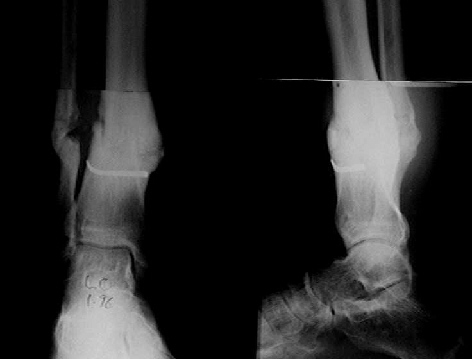

Pic attached - the transarticular K wire/steinman pin was put in by the previous surgeon, to stabilise what was apparently a very unstable

ankle.

I don't have his pre-distraction pics, but take my word for it, the ankle space was seen, though hazy, and the patient had pain on attempted movts of the ankle.

Mangal Parihar

Кликните для загрузки файла kjj.jpg